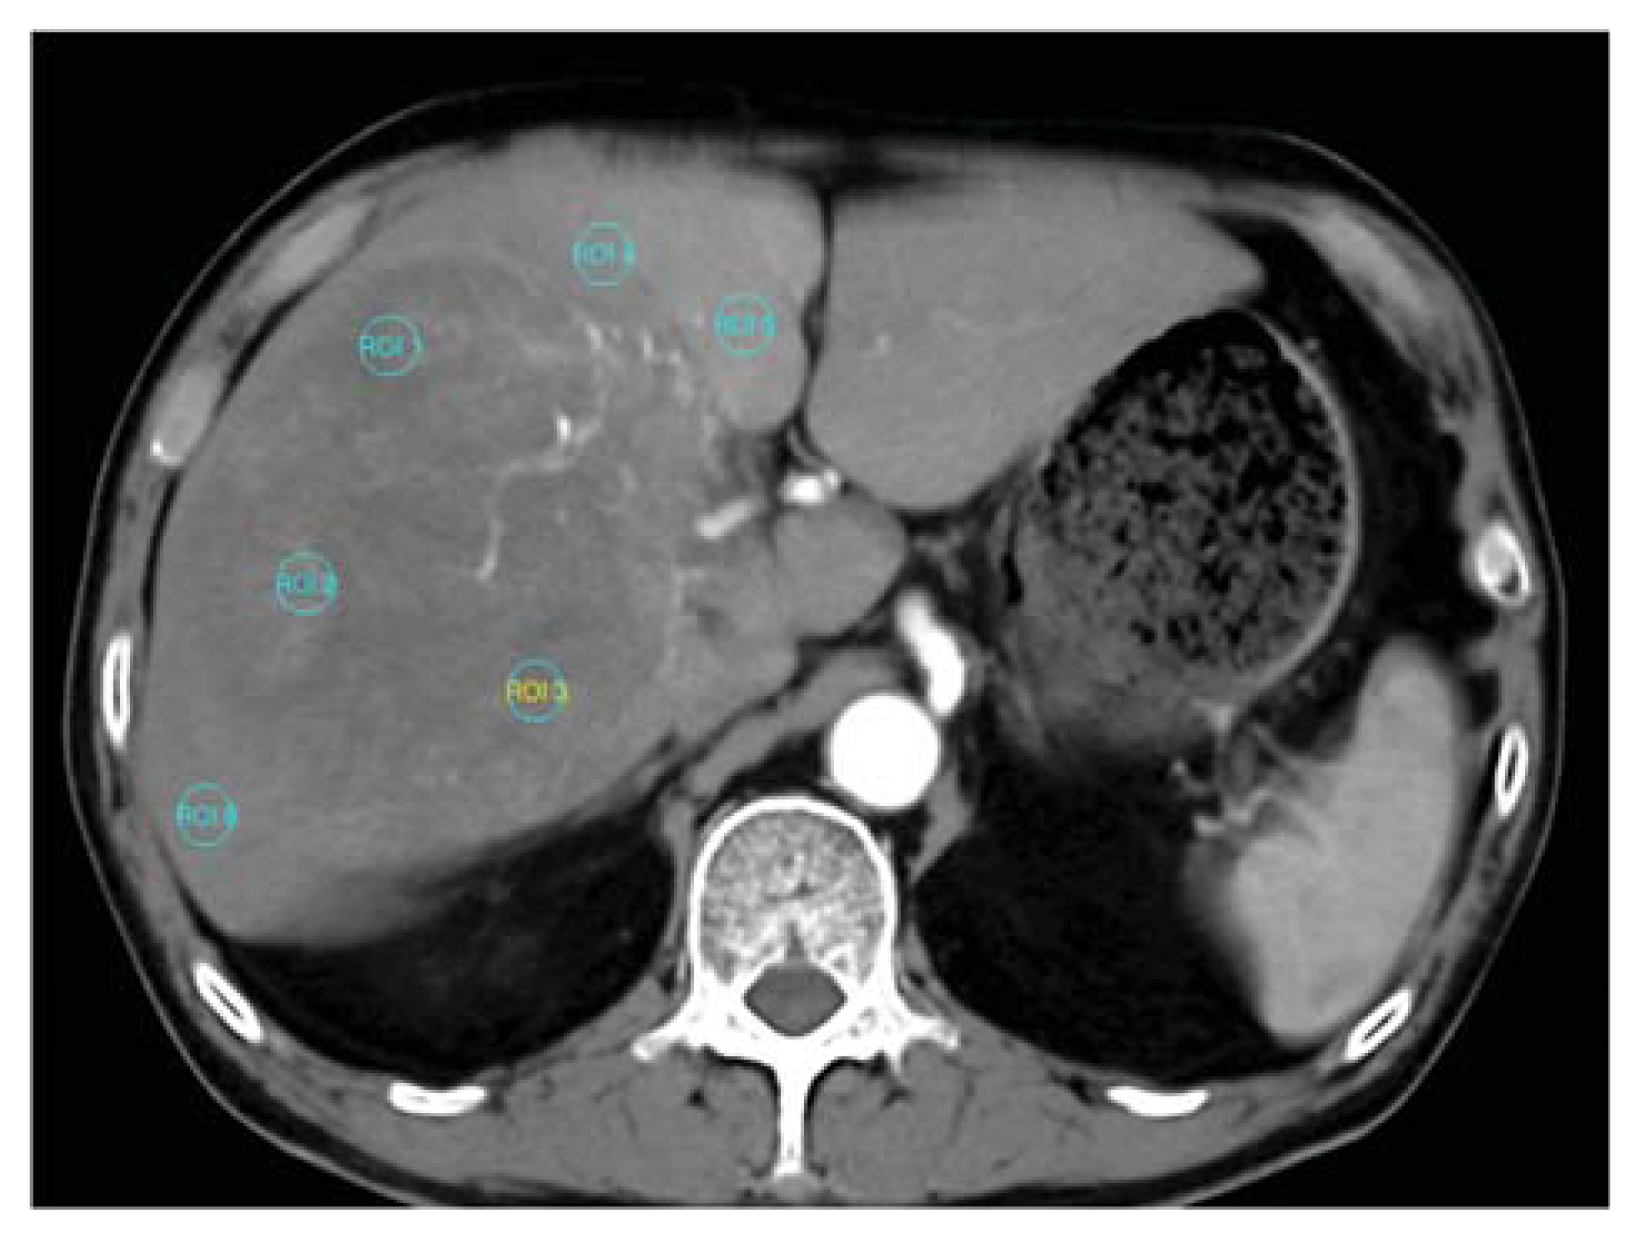

Functional maps were obtained by (a) performing motion correction; (b) adjusting an appropriate window level for the liver vessels; (c) selecting sections between the beginning and end of contrast enhancement in the aorta and portal vein automatically or manually; (d) obtaining the reference arterial and portal venous input curve by placing an ROI in the aorta and portal vein respectively; (e) generating color-coded functional maps of CT perfusion; (f) drawing three similar-sized ROI areas (1 mm2) for each of the selected target HCC and surrounding non-tumor liver parenchyma (Figure 8); and (g) calculating the average perfusion parameters at an ROI region. The operators avoided areas of necrosis in the tumor and kept a distance from the margins of the tumor nodule to avoid partial volume effects. For tumor and liver parenchyma measurement, the operators kept out of ROI observed vessels filled with contrast agent. The size of the ROI remained constant in different measurements and in different patients. To compare the relative difference of vascularity between HCC and surrounding liver parenchyma, we measured the average CT perfusion parameters of HCC relative to background non-tumor liver parenchyma and calculated the ratio of BF parameters between the HCC and liver parenchyma (HCC-parenchyma ratio). The HCC-parenchyma ratios of BF were calculated using the BF data of HCC divided by that of the surrounding liver parenchyma.

Figure 8.

Six similar-sized region of interest (ROI) areas (1 mm2) are shown for measuring the CT perfusion BF of target HCC (ROI 1–3) and the adjacent non-tumor liver parenchyma (ROI 4–6).